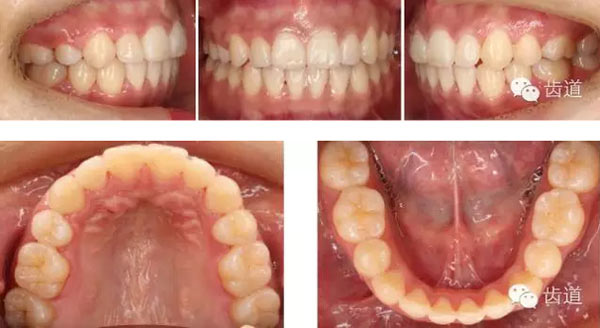

—上中線左偏,下中線右偏

—咬合平面右低左高

—前牙開(kāi)合

—右側(cè)磨牙近中關(guān)系,尖牙遠(yuǎn)中關(guān)系

—左側(cè)磨牙遠(yuǎn)中關(guān)系,尖牙近中關(guān)系

—前磨牙區(qū)及前牙區(qū)均為開(kāi)合

—右側(cè)自第一磨牙開(kāi)始至側(cè)切牙均為反合

上牙弓:尖圓形,25腭側(cè)完全錯(cuò)位,26前移

下牙弓:卵圓形,下前牙區(qū)擁擠

矯治結(jié)束后口內(nèi)像